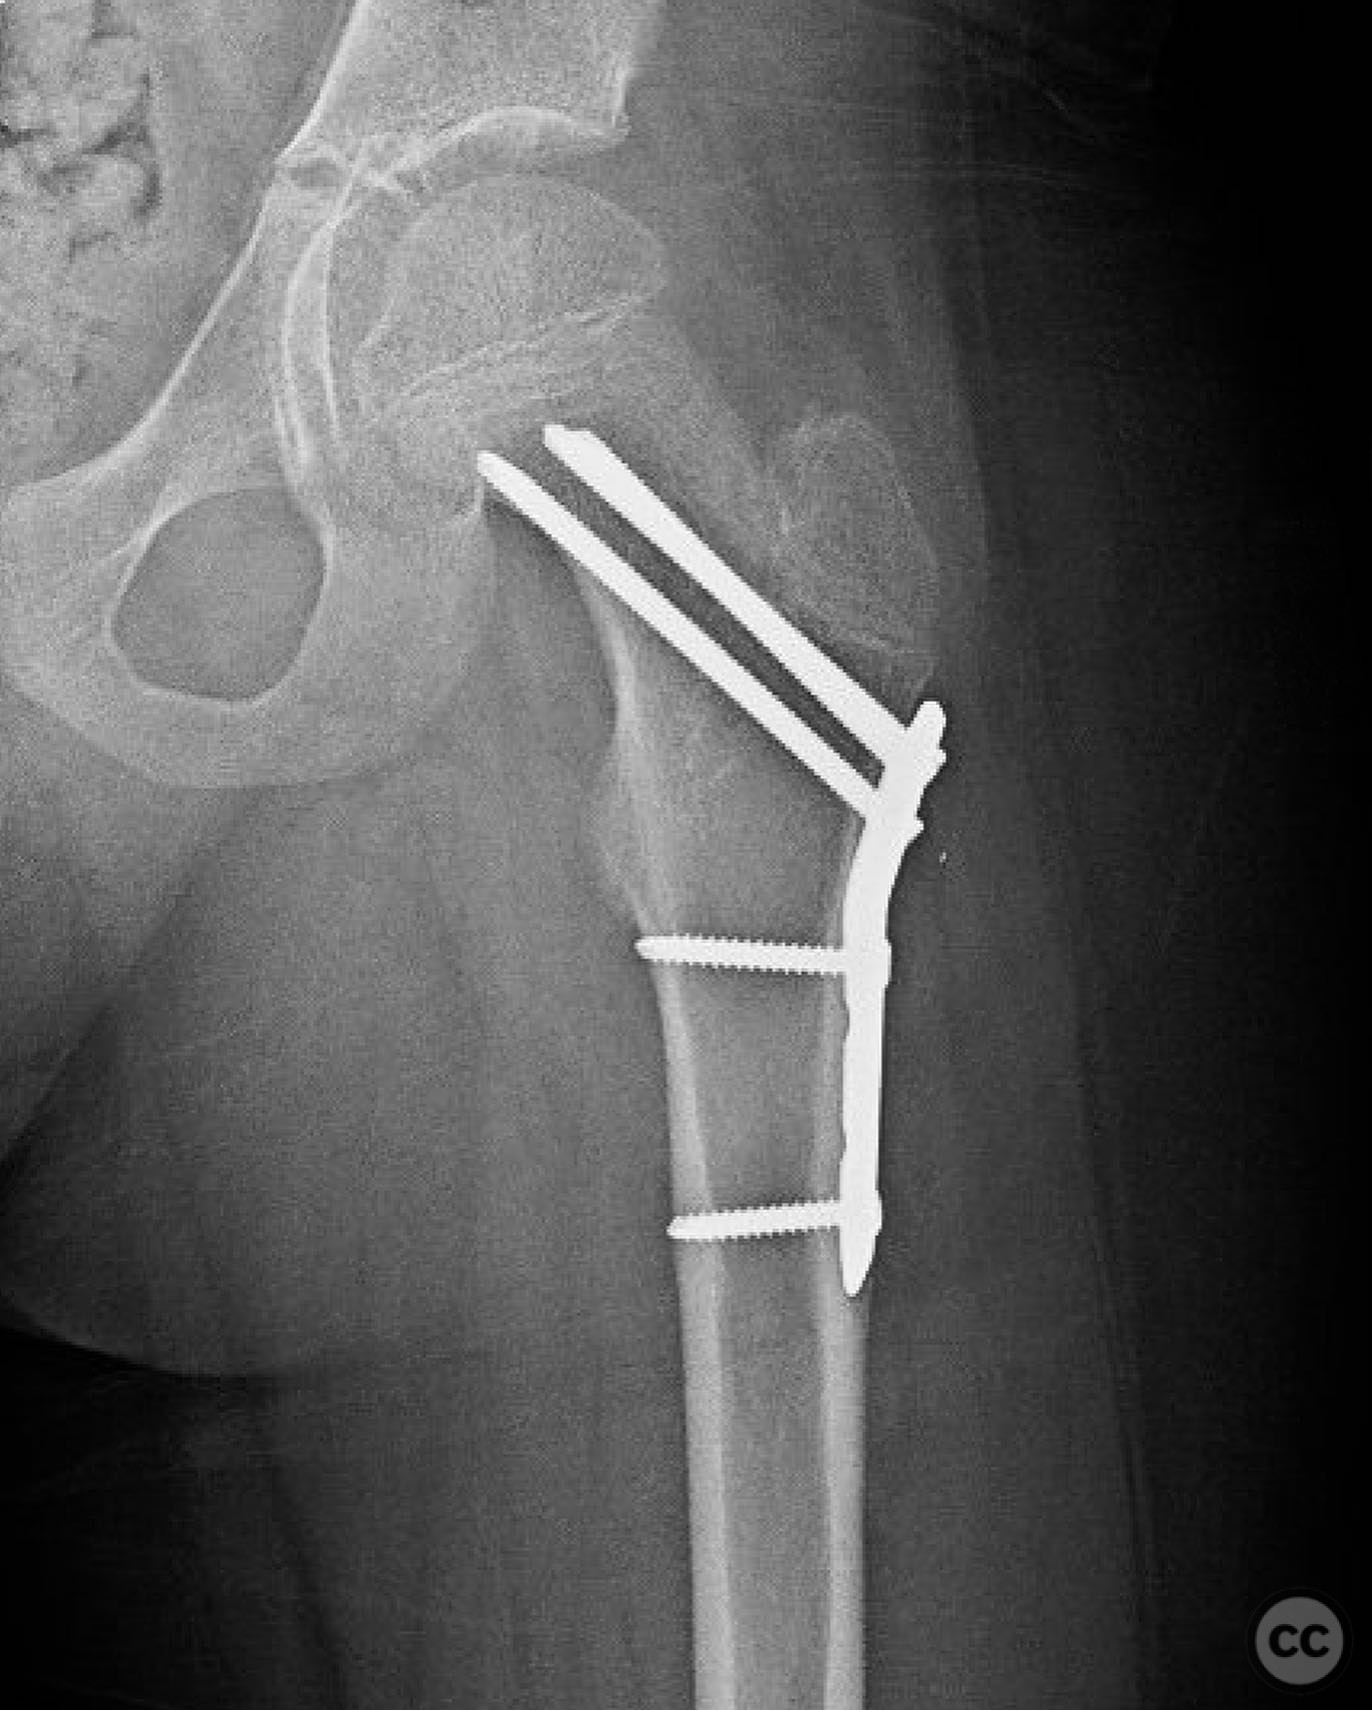

Clinical and radiological findings:  An 8-year-old boy fell approximately 15 feet from a treehouse, sustaining a displaced femoral neck fracture. There were no associated injuries to the head, spine, chest, or abdomen. The initial radiological assessment confirmed a displaced fracture of the femoral neck. Neurovascular examination was unremarkable.

Planning remarks:  The preoperative plan involved achieving a direct anatomic reduction and stable fixation of the femoral neck fracture. The surgical approach considered was a modified Smith-Petersen approach for optimal visualization and reduction, followed by a separate lateral approach for implant application.

Orthopaedic implants used:   Angle stable static device (specific brand not mentioned).